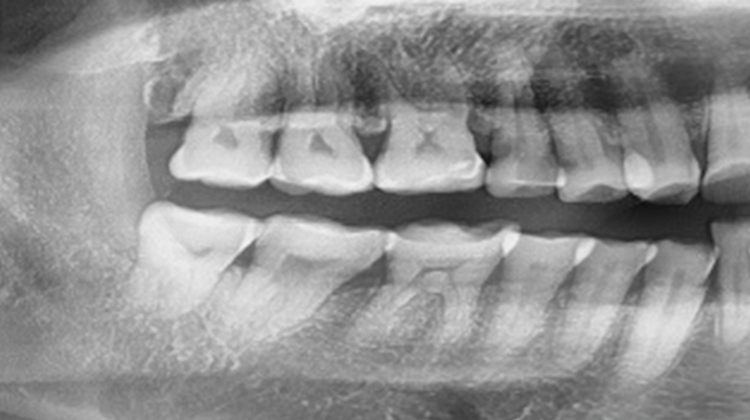

사랑니 발치 유형

- 사랑니가 밖으로 바르게 나는 경우

- 올바르게 난 사랑니는 관리만 잘하면 별다른 문제를 일으키지 않지만 칫솔이 닿기 어려운 위치에 있는 경우 충치가 생기지 않게 관리하는 것이 쉬운 일은 아닙니다. 따라서 충치 발생으로 인해 인접 치아에 해가 되거나 염증 발생, 심한 경우 구취의 원인 될 수 있으므로 충치가 발생하기 전에 미리미리 발치할 것을 권유하는 경우가 많습니다.